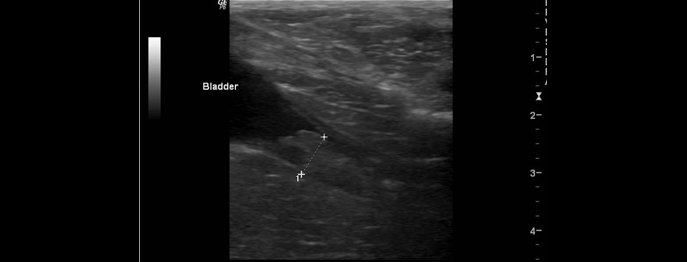

Harnblasentumoren bei Hund und Katze

Diagnostik und Therapie

Harnblasentumoren bei Hund und Katze sind insgesamt selten und treten beim Hund deutlich häufiger auf als bei der Katze.

In der Praxis stellen sie eine wichtige Differenzialdiagnose bei chronischen oder rezidivierenden Harnwegsproblemen dar. Aufgrund unspezifischer klinischer Symptome erfolgt die Diagnose häufig verzögert.

Dieses vetinar gibt einen praxisorientierten Überblick über typische Tumorformen, diagnostische Möglichkeiten und therapeutische Optionen. Zudem vermittelt er die Grundlage für eine fachlich fundierte Beratung der Besitzer.